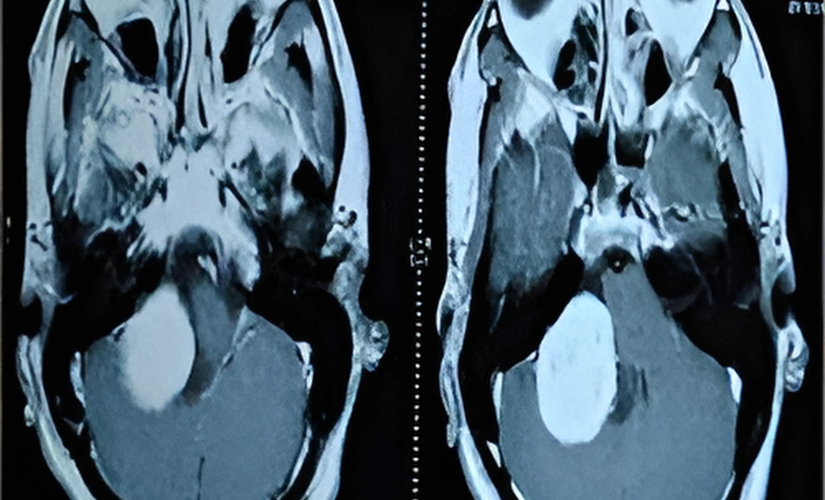

Symptoms depend on tumor size, location, and nerves affected, including headaches, facial weakness or numbness, vision changes, hearing loss, difficulty swallowing or speaking, balance problems, and hydrocephalus-related symptoms like nausea and vomiting. Diagnosis usually involves detailed neurological examinations along with imaging modalities like MRI and CT scans to map tumor extent and involvement of adjacent structures.

Through neurological exams and detailed imaging like MRI and CT scans.